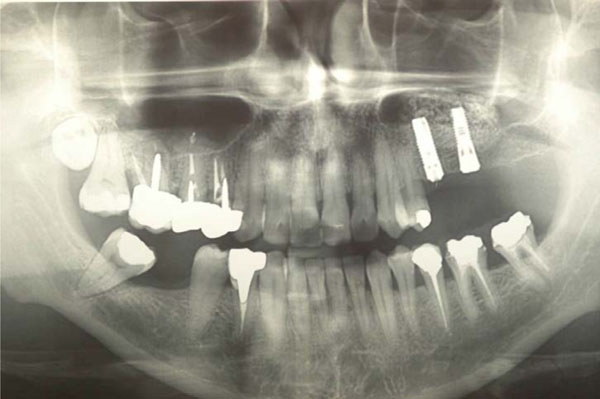

Fig. (6).

Implant insertion after 6 months. No complications were reported.